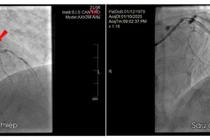

Kết quả chụp mạch vành cấp cứu tại Bệnh viện Đa khoa tỉnh Quảng Ninh cho thấy: Hẹp khít nhánh Diagonal 1 lớn, dòng chảy chậm; Hẹp LAD2 (nhánh xuống trước 2); Động mạch mũ (Cx) hẹp lỗ đổ khoảng 50%; động mạch vành phải (RCA) giãn khổng lồ.

Ngay trong đêm, bệnh nhân Hà Huy H. được các chuyên gia Bệnh viện Đa khoa tỉnh can thiệp đặt stent mạch vành cấp cứu thành công. Sau can thiệp, mạch - huyết áp ổn định, tỉnh táo, hiện đang hồi phục tốt tại Bệnh viện đa khoa tỉnh.